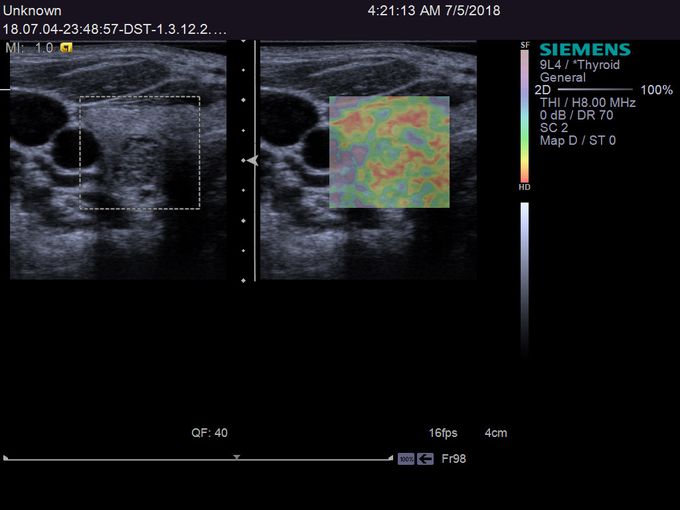

Кроме новой техники, можно заказать восстановленные медицинские системы: ультразвуковые сканеры, томографы, флюороскопы, ангиографы и хирургические установки С-дуга.